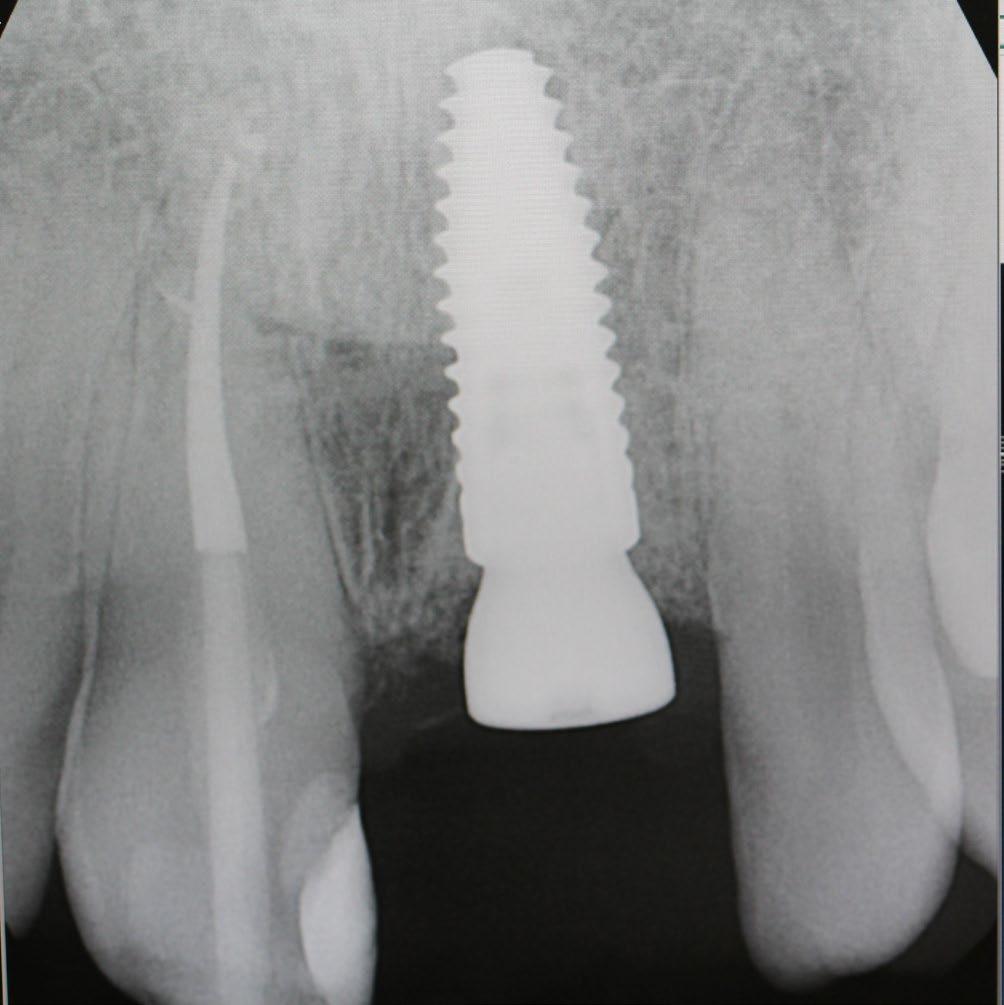

What are Dental Implants?

Dental implants are titanium posts surgically inserted into the jawbone, where they serve as a sturdy anchor for replacement teeth. Unlike dentures or bridges, which rest on top of the gums, implants integrate with the bone, a process known as osseointegration. This integration stabilizes the implant and makes it a permanent fixture in the mouth. The result is a replacement tooth that looks, feels, and functions like a natural tooth.

Creating a New Look with Dental Implants

One of the most significant advantages of dental implants is their ability to restore a natural-looking smile. They are customdesigned to match the natural color and shape of the patient’s existing teeth, blending seamlessly into the mouth. This can dramatically improve a person’s appearance, making them look younger and healthier. For many, this can lead to a renewed sense of self-esteem and vitality, particularly important as they age.

Implants act like natural tooth roots, promoting bone growth and preventing bone loss. Maintaining this bone structure not only supports facial features but also prevents the aging appearance that often accompanies tooth loss.

Long-Term Benefits and Oral Health

Dental implants also contribute positively to long-term oral health. They help preserve the jawbone and maintain the integrity of facial structures. When teeth are lost, the jawbone can gradually deteriorate because there is no tooth root to stimulate bone growth.

Moreover, unlike bridges and dentures, which often require the reduction of other healthy teeth to accommodate the appliance, implants do not compromise the health of neighboring teeth. This preservation of natural teeth is crucial for maintaining longterm dental health.